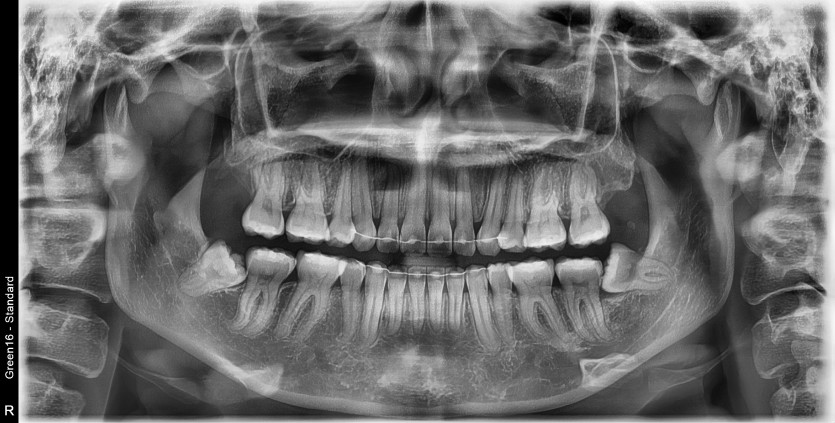

#38 사랑니 발치

구강 외과 전문의가 당일 발치했습니다.